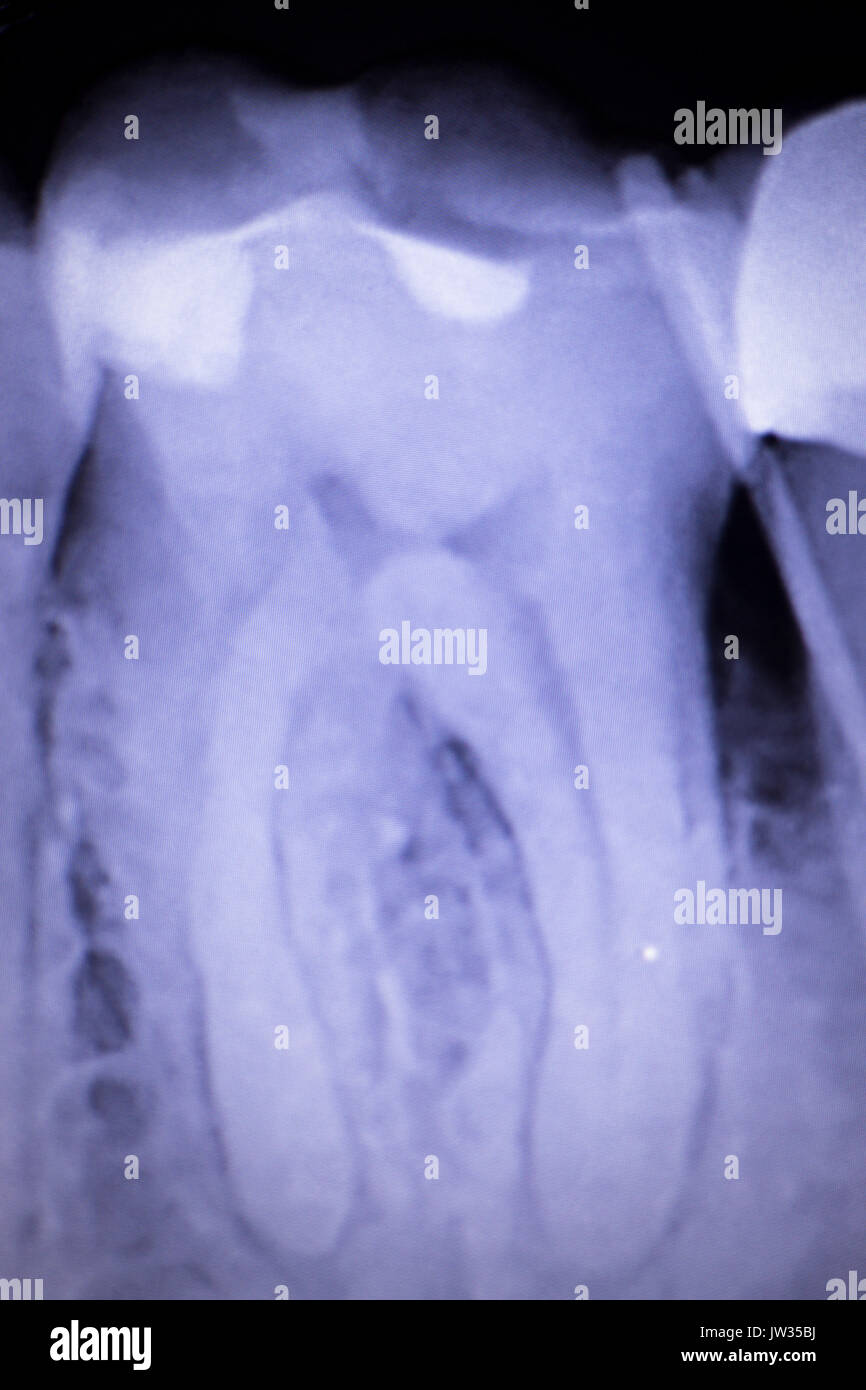

Dental xray test scan of tooth with crown filling and root canal

Dental xray test scan of tooth with crown filling and root canal X Ray Of Tooth With Filling There is no real explanation for it usually. Dental cavities are one of the most common worldwide dental problems, affecting millions yearly. Here is a picture of what a different tooth with decay underneath of an existing filling looks like. They are able to diagnose issues like cavities early and fix them quickly, helping patients avoid unnecessary pain, cost, and. X Ray Of Tooth With Filling.